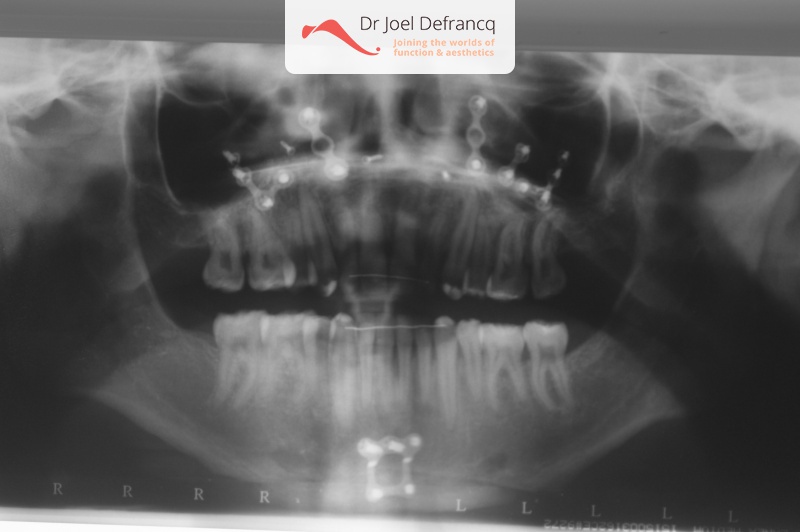

Kaakchirurgie

- Vertikale verkorting bovenkaak (Le Fort I)

- Kinchirurgie